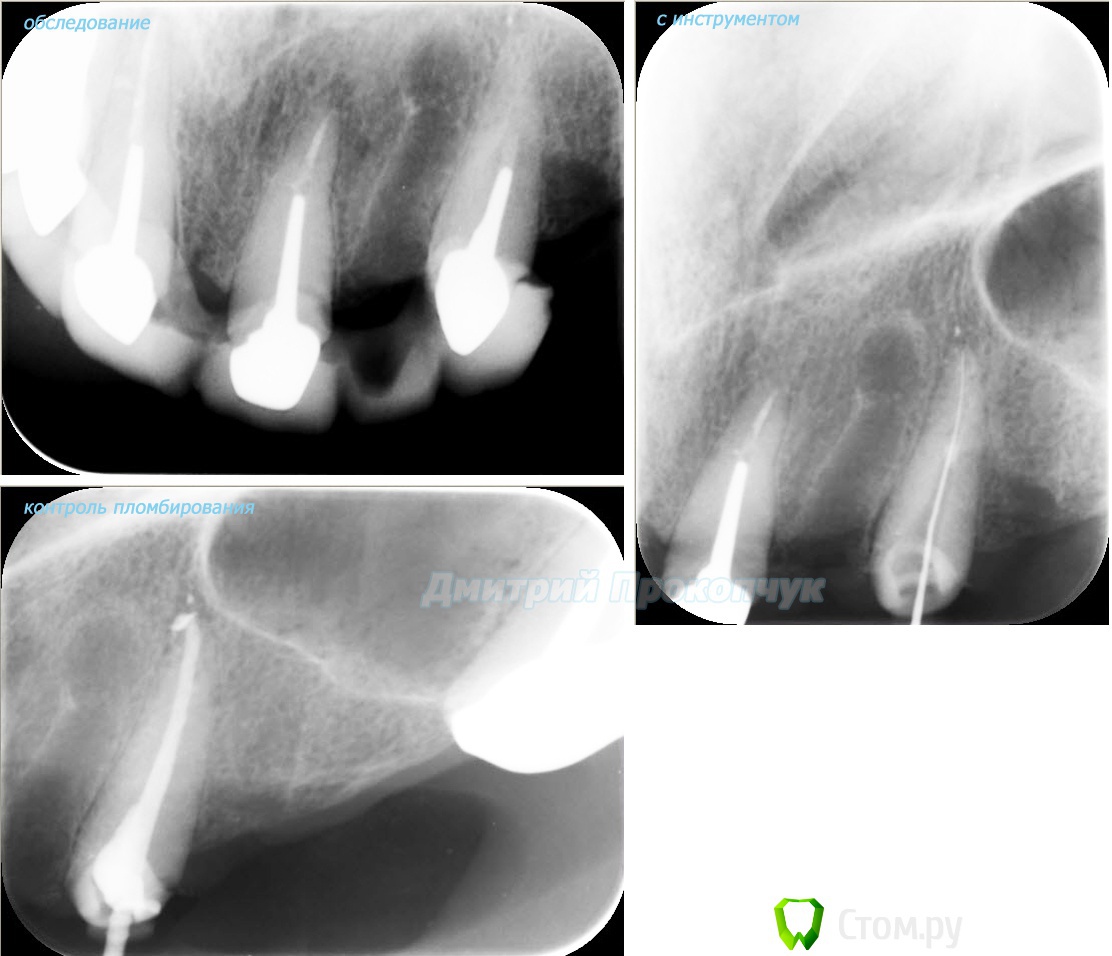

punkrat Опубликовано 16 сентября, 2014 Поделиться Опубликовано 16 сентября, 2014 Коллеги, тема , возможно, не имеет смысла просто приятная мне эндодонтия, сохранил с предыдущего места работы. Да, будь я проклят, я все знаю, НИГДЕ НЕТ КОФЕРА, на новом месте с этим норм. В общем если посчитаете, что я недостоин постить тут свои снимки, то так тому и быть, удалю тему.. 01. плановый ретрит 46ого и результат через 7 месяцев. Осложняющим моментом тут было то, что длина каналов была около 26 мм... 02. первичное эндо 34 (подготовка к ортопедии) + бонус - ретрит 35 03. ретрит 26 (подготовка к ортопедии) 04. ретрит 15, 16 (подготовка к ортопедии). основная сложность была в ретрите 15 - он был запломбирован термафилами, да еще снабжен свш... 05. ретрит 27 (подготовка к ортопедии). Ничего особенного, со временем посмотрим какова будет убыль этого совсем немаленького разрежения 06. ретрит 13. Разумеется пришлось выбивать вкладку, а потом еще попилить 3-4 миллиметра цемента, но, таки попилил куда нужно... 07. ретрит 17 (подготовка к ортопедии). В данном случае я, кажется, потратил больше времени на снятие литого моста, чем на лечение 17)) 08. ретрит 16 (подготовка к ортопедии). Снимка с инструментом нету, поскольку, визиограф сломался и его делал на пленку. 15 разумеется тоже перелечен... 09. плановый ретрит 16 10. первичное эндо 36, рядовой случай что дистальный щечный удалось найти не сразу, он был спрятан под нависающим дентиклем 11. ретрит 12, 11 (подготовка к ортопедии). Казалось бы, рядовой случай, если бы корневые каналы обоих зубов не были бы налухо забиты резорцин-формалиновой смесью... 12. ребенок 9ти лет, острый пульпит 46, попробовал оставить витальным. Пока полет нормальный, но даже если придется делать эндо в последствии, лучше когда оно будет сделано в более старшем возрасте... 13 Ссылка на комментарий